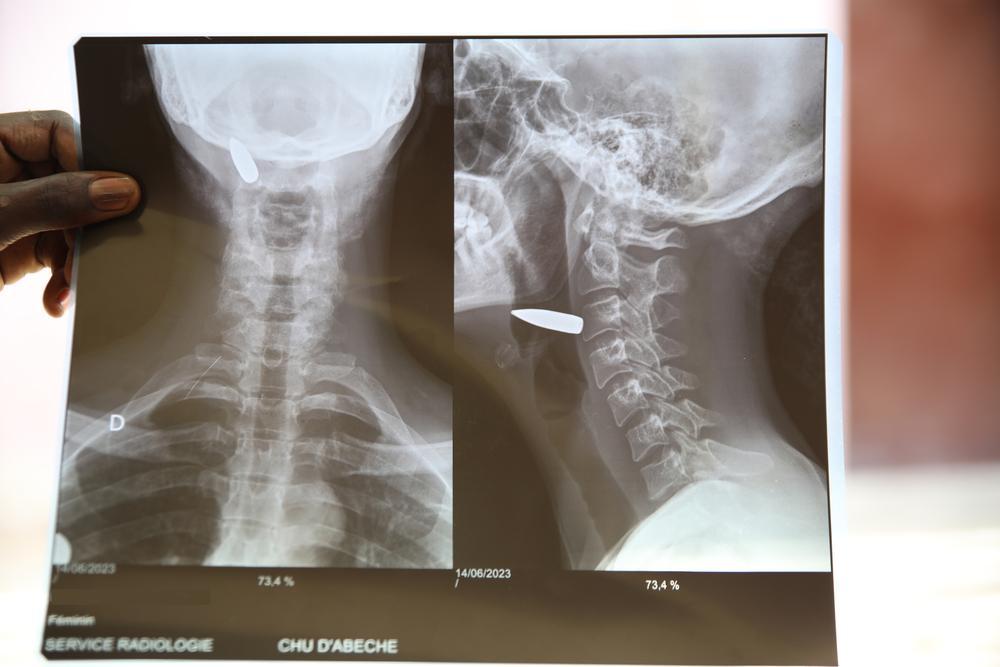

Les conflits armés détruisent des vies. Prises pour cibles, harcelées et piégées dans la misère et la pauvreté, les personnes sont souvent contraintes de fuir. Dans d'autres cas, elles vivent en état de siège ou dans la crainte constante d'attaques aveugles ou même ciblées. En outre, les gens sont souvent appauvris et n'ont pas suffisamment accès aux besoins de base tels que la nourriture et les soins médicaux. Une aide médicale et humanitaire complète est vitale, mais les services de santé sont souvent rares. Dans les zones de conflit, nous ne prenons pas parti.

Les civils doivent être protégés et les organisations humanitaires doivent pouvoir travailler, cela veut dire épargner les structures hospitalières et créer des couloirs humanitaires, afin de pouvoir transporter du matériel médical, mais aussi des patients et des blessés ».